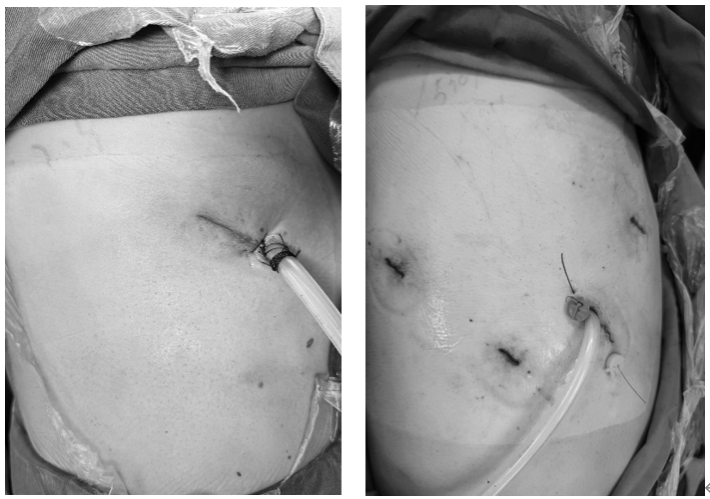

纯单孔机器人肺叶切除术(左)对比常规四孔机器人手术(右)切口及引流管照片

在机器人手术团队的通力配合下,历时105分钟,北京地区首例纯单孔机器人肺叶切除+淋巴结清扫术,顺利完成。经过3天左右的术后康复,患者顺利拔管出院,恢复良好。